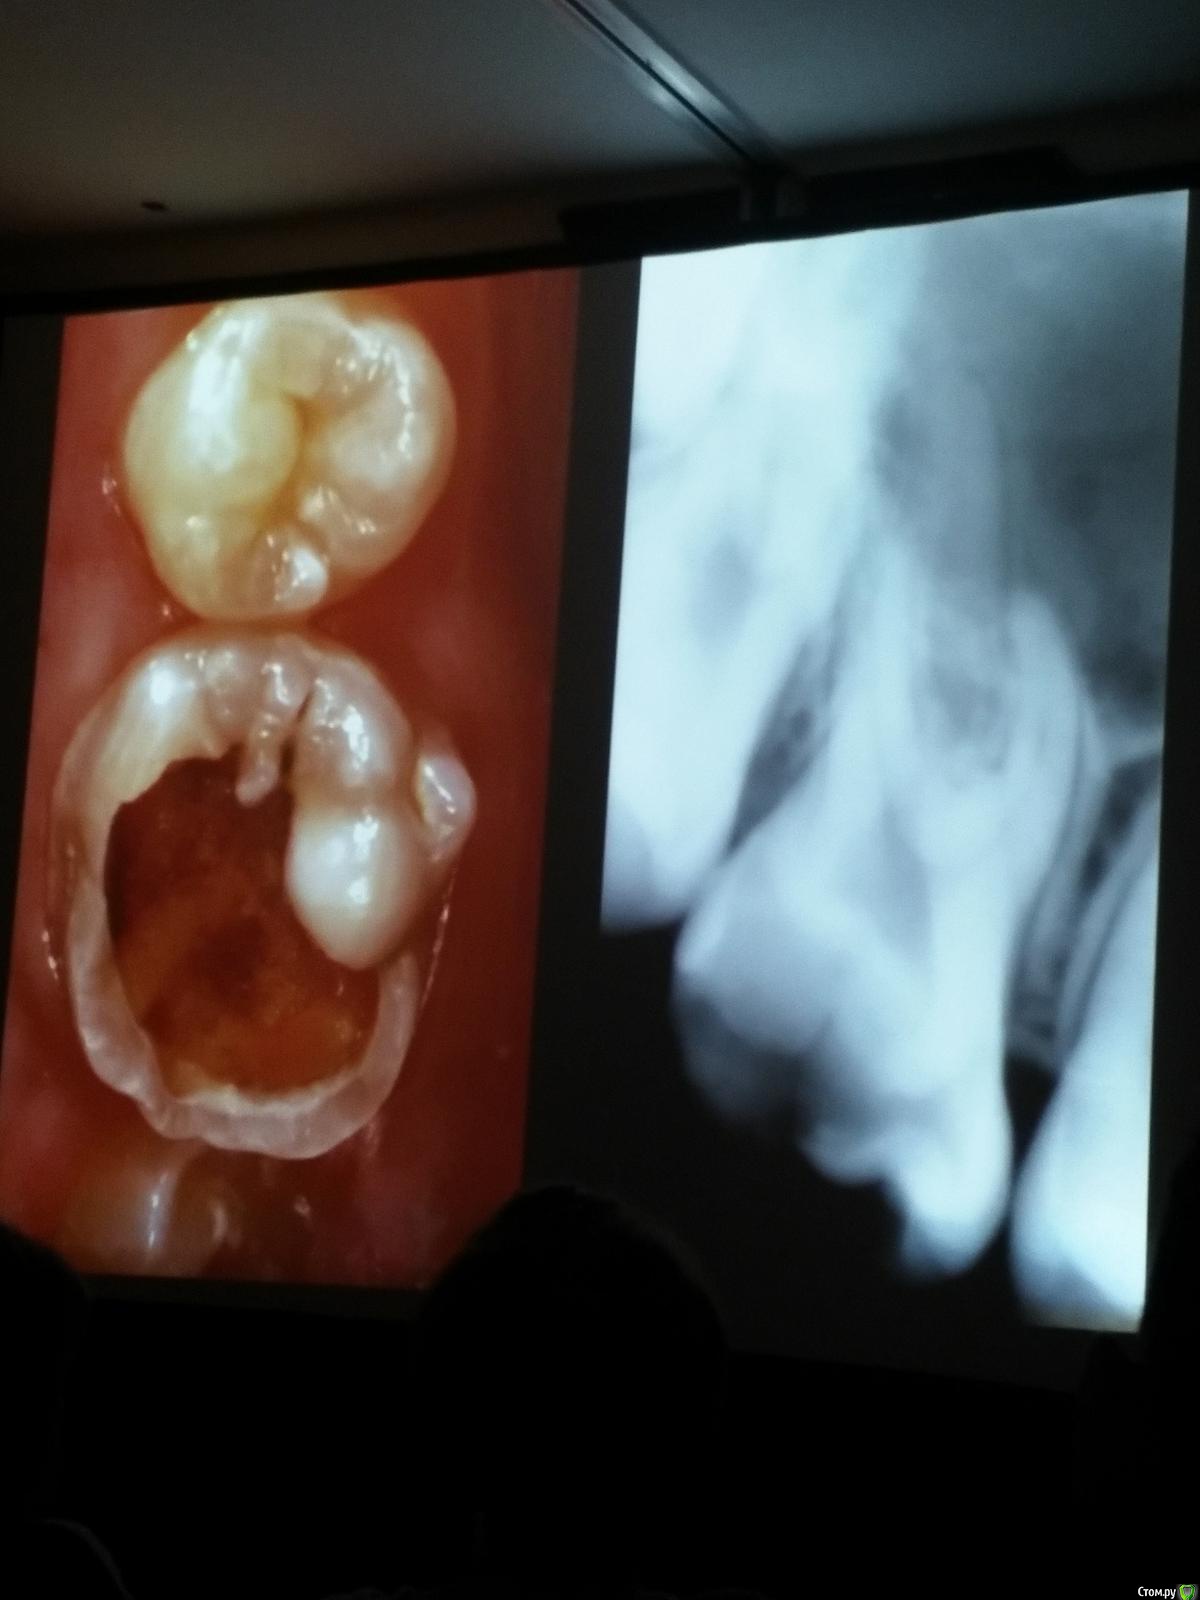

Популярный пост Kolchanov Опубликовано 11 марта, 2017 Популярный пост Поделиться Опубликовано 11 марта, 2017 (изменено) Товарищи, скажу я вам...........Вкратце. Может я где-то что-то и приврал, надеюсь, кто еще был, поправят. Честно говоря немного прибалдел от уровня Доктора. Очень, очень высоко! Приедет еще раз, пойду еще. 1) Фиссуры зондирует острым зондом и выпиливает все дотла. По факту у него уже пломбы, а не герметизация.2) Bite-wing у первичных пациентов всегда.3) Если кариес диагносцирован, то лечить его, пофиг какой он там. Эмали, дентина…4) Препарирует до твердого (или до вскрытия J ). CAD, СID… в топку. Кариес маркером не пользуется, проверяет острым зондом/экскаватором. Вычищает все дотла. Считает, что даже небольшое количество бактерий в дентине под пломбой вызывают хроническое воспаление в пульпе. С его слов у него на контроле где-то 500 вскрытий, не удивительно при таком подходе к очистке.5) Тщательная изоляция. Коффер порвался – меняет. Большое значение герметичности реставрации. под замену6) Критерии обратимости и необратимости.Гистологически, обратимый тот, что без абсцессов в пульпе, но клинически это понять нельзя, только предположить.Здесь был бы обратимый, если бы не удалил. Нет микробов в пульпе. Линия - граница обработки.Покрытие 27 лет назад. Dycal, СИЦ, композит. От дайкала одно воспоминание.7) Вскрылись. Размер перфорации, возраст и прочее не играют роли, важно только состояние пульпы, т.е. диагноз.Примеры перфораций.8) Кровотечение останавливает стерильным ватным шариком. Если останавливается, то покрытие, если нет, то пульпотомия или пульпэктомия.9) Использует гидроокись кальция (порошок), перекрывает Dycal или СИЦ. Потом восстановление Нередко под IRM, потом все убирает (через пару-тройку месяцев) и смотрит, что получилось. Порой приходится повторять! Использует и МТА, его тоже убирает.10) Наблюдение 6мес, 1 год, 2…. Все может провалиться и через месяц и через 24 года.Примеры проваловНиже - 24 года спустя появилась дуля. 11) Неравномерная облитерация полости зуба на RG (после покрытия) – признак текущего хронического воспаления, где-то остались микробы. Рекомендует эндо.12) Мостик который образуется – это не дентин! И одонтобласты не регенерируют и новые не образуются. Что это такое он и сам не знает, но раз это твердые ткани, то и наплевать.Вот фиолетовое это дентинные опилки вмурованные в розовую ткань бог знает кем сформированную.13) Пульпотомия в зубах с несформированной верхушкой и в сформированных, при подозрении на частичное поражение коронковой пульпы. Иссекается стерильным алмазным бором часть пульпы, гидроокись, временная пломба на 90 дней, после повторное раскрытие, оценка результата, восстановление в случае формирования твердых тканей. Гипохлоритом можно мыть, можно не мыть, если мыть, то 0,5-1%.14) В апикальной части пульпа чаще витальна, чем нет.15) Периапикальные поражения возникают по причине поступления токсинов микробов с током крови, а не самих бактерий.16) За апикальные расширения в полностью некротических случаях. Надо механически отодрать биопленку и срезать инфицированный дентин. На ирриганты надежды мало.17) Биопленка на поверхности в 6% случаев.Синенькие пид@расы18) Обработку проводить нежно, краун-даун. Чередовать с H-файлом, чтобы посмотреть докуда распространяется некроз.19) Патенси в витальных кейсах не колоть, сохранять витальную пульпу в констрикции!Формирование еще большего сужения в констрикции за счет сохранения витальной пульпы. Изменено 11 марта, 2017 пользователем Kolchanov 31 Ссылка на комментарий

Популярный пост Kolchanov Опубликовано 12 марта, 2017 Автор Популярный пост Поделиться Опубликовано 12 марта, 2017 Второй день.1) Дезинфекция зуба и раббер дама перед работой. Вначале установка системы, потом протирка тампоном 30% перекиси, потом протирка всего йодинолом. Потом преп, потом повторение и только потом доступ к к/к. Все старые реставрации надо убрать, кариес убрать, противник лечения через коронку.2) Гидроокись на неделю. Замешивает на стерильном физрастворе. При необходимости повторяет. Т.е. в случае сохранения свища, симптоматики, экссудации, запаха. Если свищ не исчезает после трех смен временных вложений, то хирургия.3) Пломбирует латеральной компакцией. Лучше контроль длины обтурации.4) Высушивание канала стерильными штифтами, на рабочую длину минус 1мм. После высушивания штифт оставляется на 60с. в канале и должен выйти сухим.5) Определение рабочей длины. Витальные случаи. АЛ должен три раза дать одну и ту же картинку в определенной точке + проверка RG. Девитальные случаи. На АЛ полагаться сложно, т.к. из-за наличия резорбции констрикции может врать, больше ориентируется на RG.6) Использует ЦОЭ силеры. Резорбируются при незначительном выведении. Резорбируются в канале, позволяя закрыть апекс цементоподобной тканью. Вот так вот.Случаи исчезновения силера, как за пределами канала так и в канале7) Выведение материала (не важно какого) в большом объеме способно вызвать защитную реакцию тканей. Которая должна пройти спустя некоторое время. (иногда это будет 25 лет J Случай 1ый. Студенты наломали инструментов. Периодонтит на RG через год. Резекция и гистология. Бактерий не обнаружил. Да, маленькое замечание. Каждый препарат дает 500-600 срезов. И ищет он на всех. Объем работы, конечно….Случай 2й. Его собственный. Периапикальное поражение, обнаруженное на реколле через 10 лет зажило еще через 15.8) «Функционирующий зуб» считает результатом неприемлемым. Осталась инфекция с которой надо что-то делать. То, что бактерий можно замуровать в дентинных трубочках и под пломбировочным материалом, считает неправильным. Продукты метаболизма один фиг будут просачиваться и могут поддерживать реакцию воспалительную.Случай. Синее – маленькая кучка микробов, предположительно, препятствовавших заживлению очага.9) Биопленка на поверхности корня может принимать вид кальцификатов (камней) и тут уже только хирургия в помощь. При длительном существовании свищевого хода, например.Черное - это камни вокруг апикального отверстия. И гистология их с кучей синих микробов.Здесь камни на фуркации и отсутствие заживления и свищ даже после ретроградной обработки и пломбировки.А здесь вообще чертова уйма камней. И зацените разветвление канала в этом боковом резце (последнее фото препарата). 10) Реваскуляризация.В некротических случаях дентина не образуется, т.к. одонтобластов нет и не будет новых. Образуется та самая бог знает какая ткань, которая даже и с корнем не связана может быть. Суть здоровый дентикль-петрификат. А в витальных это не реваскуляризация, а обычное формирование корня. Так что нечего тут.11) Трещины дентина.Советует расшивать, братья и сестры. Без фанатизма, если нет симптоматики, но, по возможности максимально. Если есть симптоматика, то там уже по обстоятельствам. Чертова уйма микробов там и ползет, ползет к пульпе. Надеюсь, что еще раз этот замечательный Доктор приедет. Схожу с удовольствием. 2 23 Ссылка на комментарий